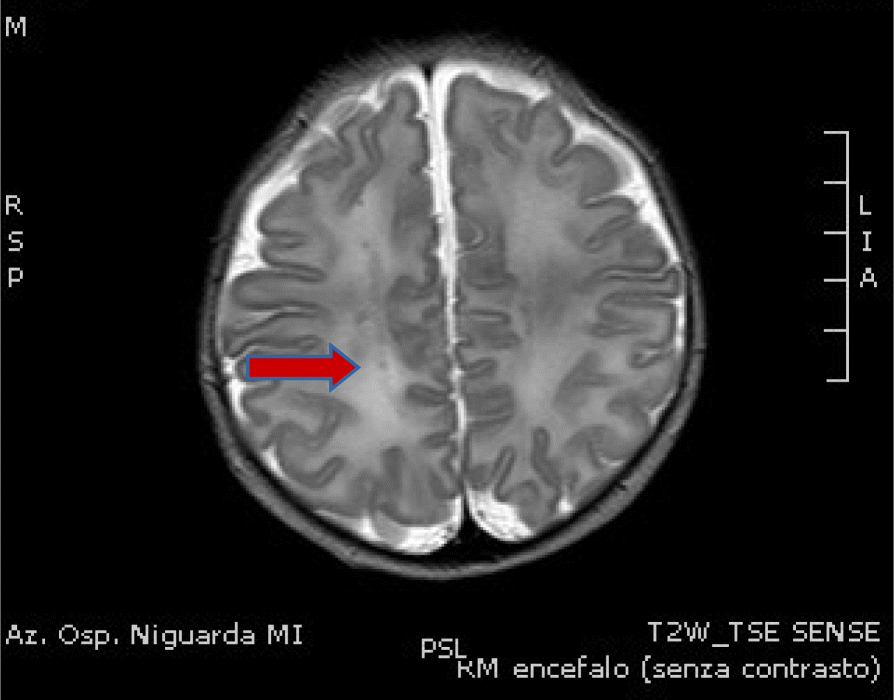

Fig. 1(abstract A19).From: Proceedings of the 33rd Congress of the Italian Society of Neonatology, Lombardy Section, 31 January - 1 February 2020T2 RMN on day 10Back to article page